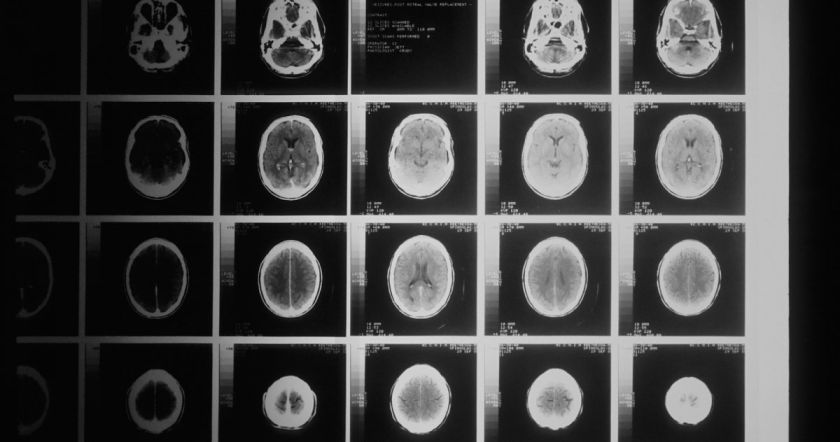

Расположение опухоли в организме влияет на тип симптомов, которые испытывает человек. Из-за сложности мозга и того факта, что он выполняет различные важные функции, любой рост органа может вызвать широкий спектр побочных эффектов.

Опухоль головного мозга в лобной доле может привести к потере обоняния (а также к другим симптомам, таким как трудности с речью, концентрацией внимания или изучением новой информации).«Опухоль головного мозга в теменной доле может привести к затруднению сбора информации от ваших органов чувств, включая обоняние и вкус (а также к другим симптомам, таким как трудности с распознаванием лиц или объектов и координацией движений)».